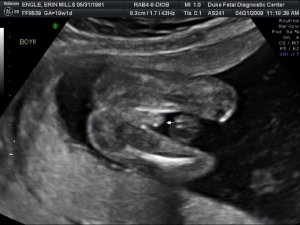

It’s a boy!

We found out the big news this morning! I really thought I would have like 8 girls and never have a boy. I am really excited, though…now just have to come up with a name! We were all set with a couple girls’ names that we like, but we still haven’t settled on a boy name yet. It will come, though. So, please begin praying for both momma and baby boy!